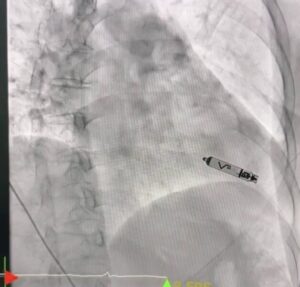

ศูนย์หัวใจ โรงพยาบาลหาดใหญ่ ประสบความสำเร็จในการรักษาผู้ป่วยโรคหัวใจเต้นช้าผิดจังหวะชนิดสมบูรณ์ (Complete Heart Block) ด้วยการใส่เครื่องกระตุ้นหัวใจชนิดไร้สาย (Leadless Pacemaker) ผ่านสายสวนหลอดเลือด ซึ่งเป็นเทคโนโลยีทางการแพทย์สมัยใหม่ และนับเป็นครั้งแรกของโรงพยาบาลในสังกัดสำนักงานปลัดกระทรวงสาธารณสุข ที่สามารถดำเนินการรักษาด้วยวิธีนี้ได้สำเร็จ

ผู้ป่วยเป็นหญิงอายุ 56 ปี ได้รับการวินิจฉัยว่าเป็นโรคหัวใจเต้นช้าผิดจังหวะชนิดสมบูรณ์ (Complete Heart Block) ซึ่งจำเป็นต้องใส่เครื่องกระตุ้นหัวใจเพื่อช่วยควบคุมจังหวะการเต้นของหัวใจ โดยคณะแพทย์ได้เลือกใช้เครื่องกระตุ้นหัวใจชนิดไร้สาย (Leadless Pacemaker) ซึ่งเป็นเทคโนโลยีใหม่ล่าสุด ทำการใส่ผ่านสายสวนหลอดเลือดเข้าสู่หัวใจโดยตรง

เทคโนโลยีดังกล่าวมีข้อดีคือ ไม่มีสายไฟเชื่อมต่อกับตัวเครื่อง ลดความเสี่ยงต่อการติดเชื้อ ลดภาวะแทรกซ้อนจากสายเครื่องกระตุ้นหัวใจ และช่วยให้ผู้ป่วยฟื้นตัวได้เร็วขึ้น